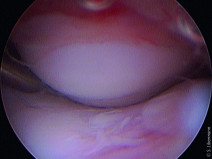

• Formation pratique en endoscopie digestive et respiratoire

La simulation sous toutes ses formes permet d’apprendre et de répéter les gestes ou les actions dans des conditions proches du réel et sans le stress émotionnel.

L’école de Chirurgie de Nancy qui possède un plateau technique dédié d'exception ouvre ses portes aux formations pratiques vétérinaires. L'intervanant, le Dr Patrick Bergeaud, pratique l'endoscopie digestive et respiratoire dep...